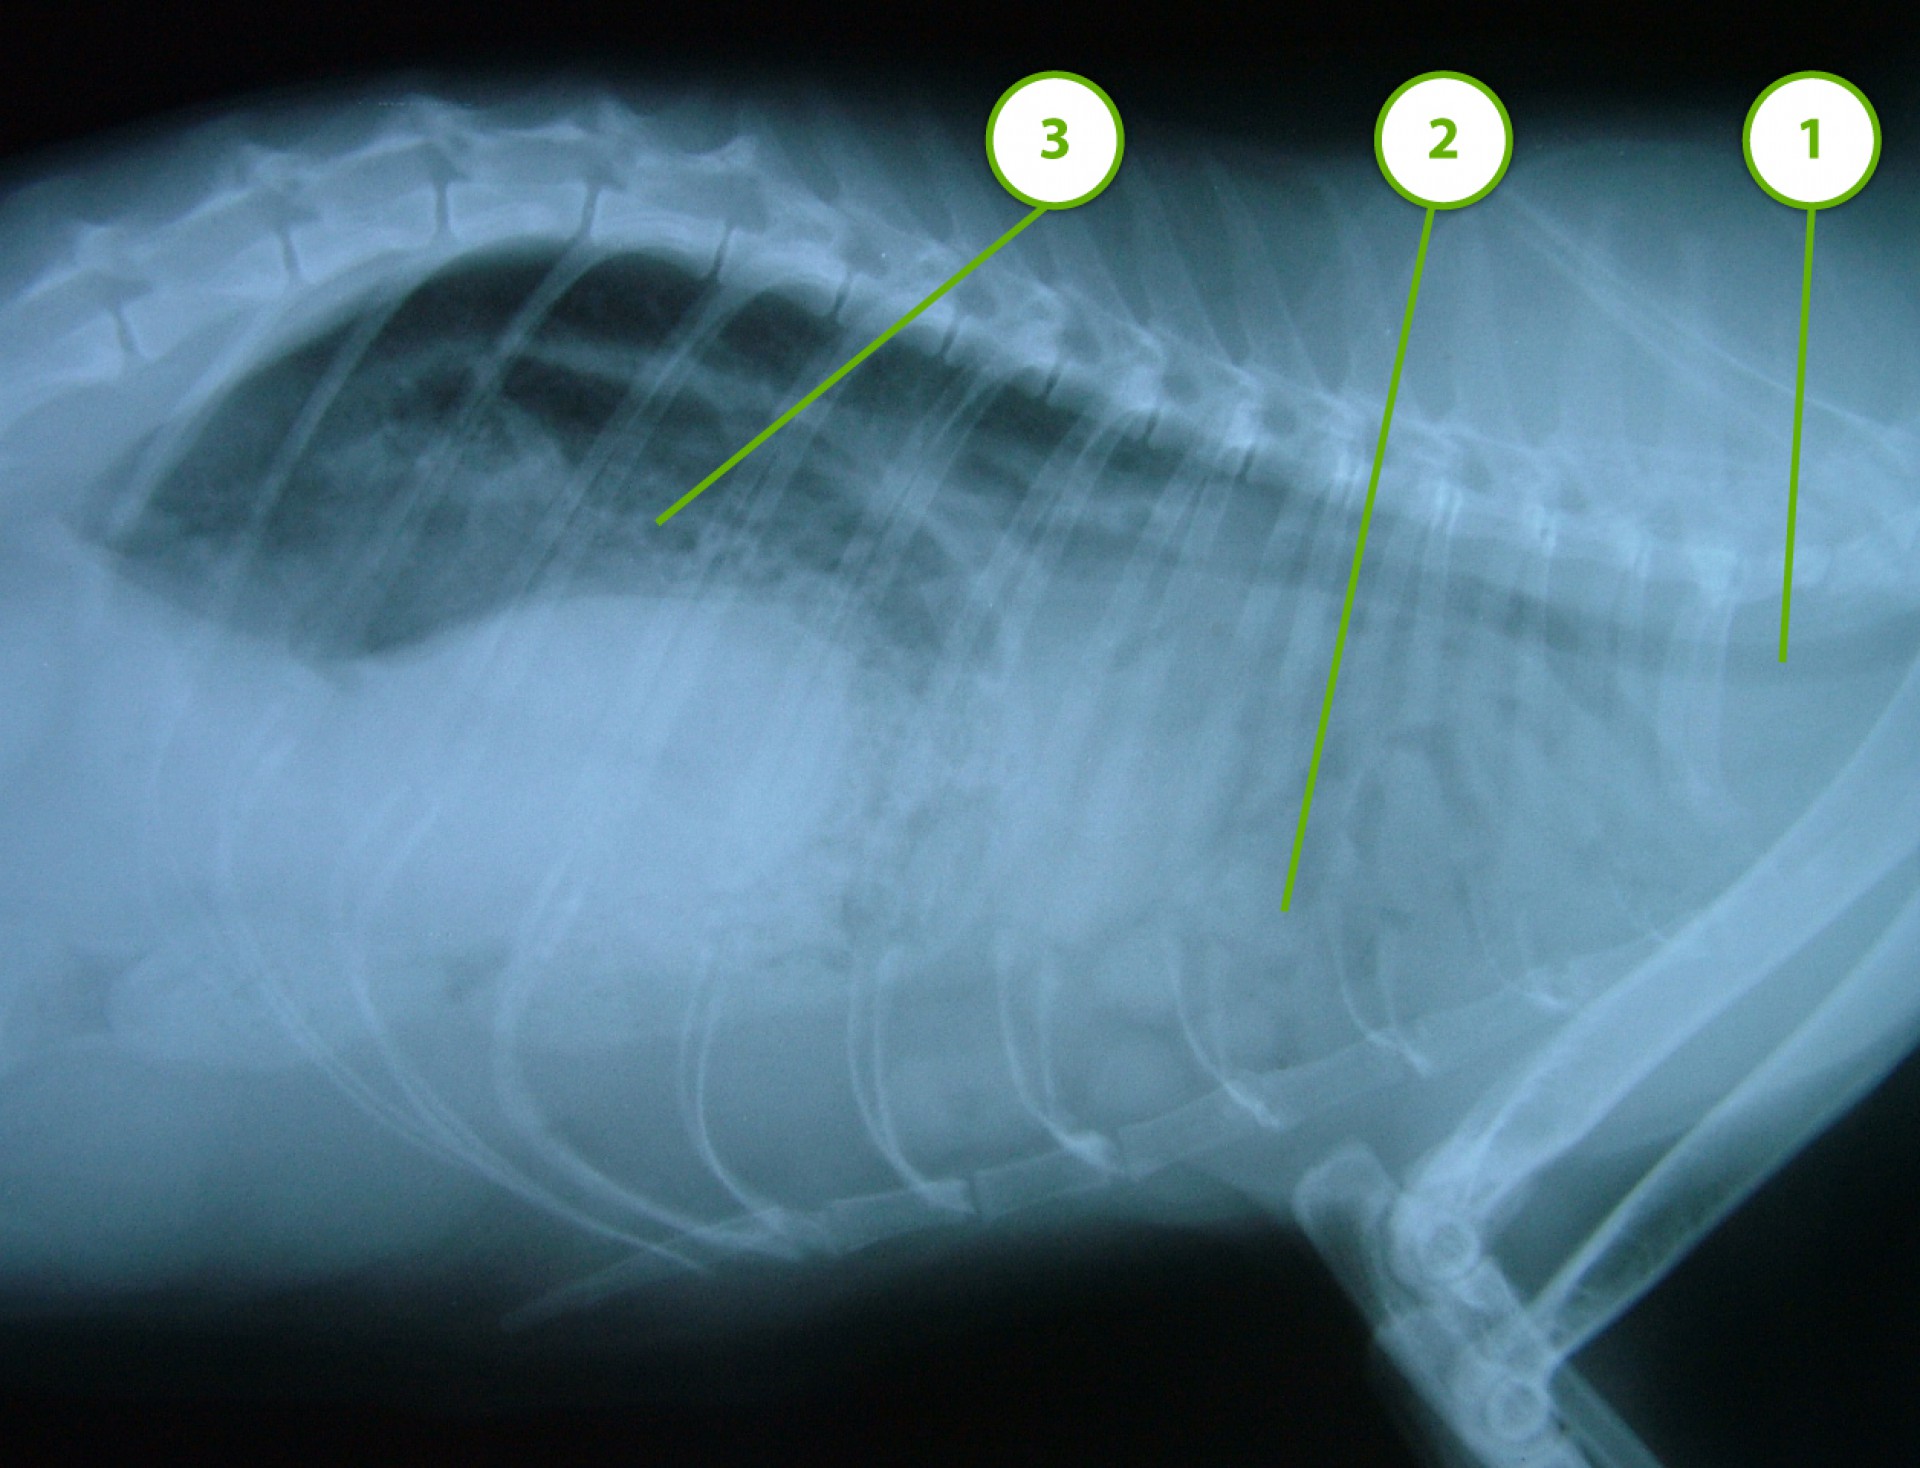

• Találkoztunk már olyan esettel is, amikor a tulajdonos a macskáját a traumát követően nem azonnal hozta az állatot ellátásra, ezért a traumás rekeszsérv diagnózisát néhány hónappal a sérülés után állítottuk fel (idült rekeszsérv, hernia diaphragmatica chronica). Ebben az esetben mérlegelni kell, hogy a hónapok alatt kialakult és stabilizálódott állapotot megbolygatjuk-e egy műtéttel vagy változatlanul hagyjuk. A műtét kockázatát ebben az esetben – a tulajdonossal való egyeztetést követően - nem vállaltuk.

Mindhárom rekeszsérv forma meglehetősen ritkán fordul elő. A diagnózis felállítása a kórelőzmény, a klinikai tünetek a mellkas röntgenvizsgálata, a hasüreg ultrahangos vizsgálata alapján lehetséges.A rekeszsérv műtéti ellátása során a legnagyobb kihívást az jelenti, hogy a hasüreg megnyitását követően a sérvkapun keresztül levegő kerül a mellüregbe, ezáltal az állat spontán légzése leáll, így a műtét teljes ideje alatt asszisztált lélegeztetésre van szüksége.A műtét során a mellkasba előesett szerveket reponáljuk, a rekesz folytonosság hiányát megszüntetjük és a mellkasban lévő szabad levegőt eltávolítjuk, ezzel biztosítva az állat spontán légzését. A műtétet követő napokban legfontosabb feladat a vérkeringés és a légzés folyamatos, kórházi körülmények közötti kontrolálása.Az idejében felismert és megfelelően ellátott veleszületett rekeszsérv jó eséllyel gyógyítható, a traumás eredetű sérv ellátásának eredményességét általában az egyéb szervek sérülése határozza meg.